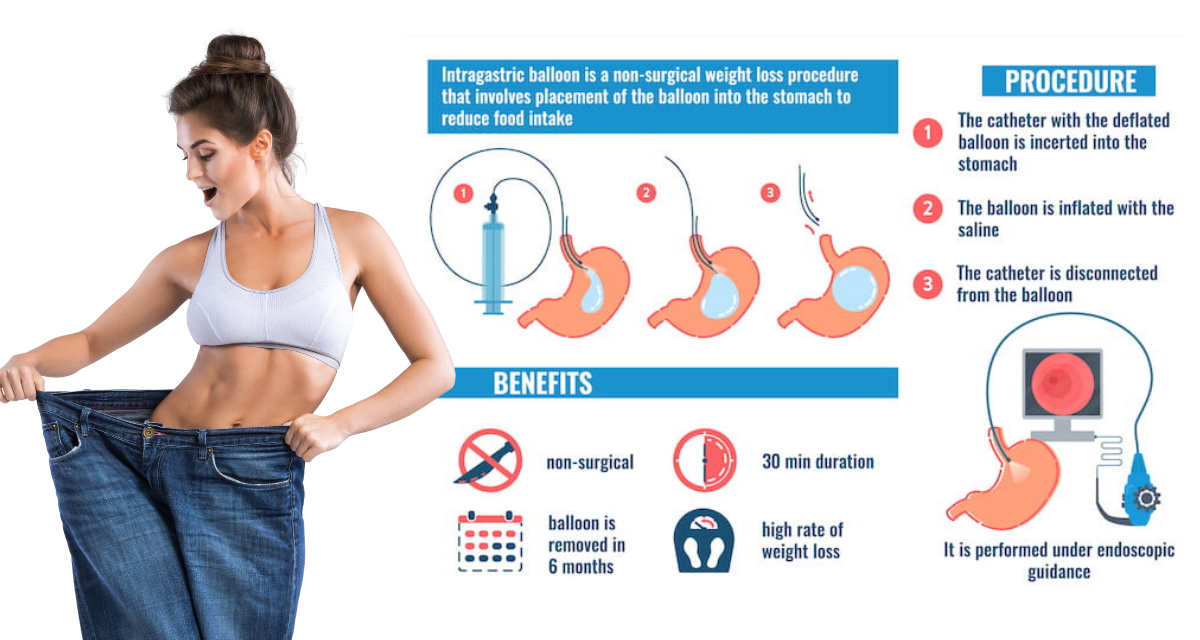

Желудочный баллон — это мягкий, гладкий и прочный баллон из силиконовой резины. Он предназначен для размещения в желудке, чтобы уменьшить его емкость и помочь вам чувствовать себя сытым при меньшем количестве еды. Сдутый баллон вводится врачом через рот в желудок с помощью эндоскопа.

Желудочный баллон – это метод, используемый при лечении ожирения и не требующий хирургического вмешательства. Это метод, который помогает похудеть за счет создания низкокалорийной среды в результате меньшего потребления пищи и постоянного насыщения благодаря баллону, занимающему объем желудка.

Это метод, который может оставаться в желудке в течение 6-12 месяцев и используется для лечения ожирения около 30 лет. При условии соблюдения диеты и программы упражнений с помощью этого метода можно ожидать потери примерно 20 килограммов веса за год.

Баллон применяется эндоскопически, то есть без хирургического вмешательства. Поскольку пациент находится под наркозом, он ничего не чувствует во время процедуры и процедура завершается в среднем за 15 минут.